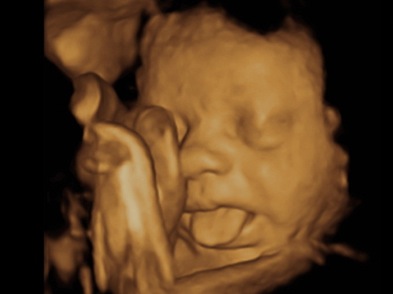

Una ecografía (sonografía) es una prueba que utiliza ondas de sonido de alta frecuencia para crear una imagen de cómo se está desarrollando un feto en el útero. También se puede usar para revisar los órganos pélvicos durante el embarazo. La imagen de ultrasonido se produce en base al reflejo de las ondas de las estructuras corporales. Al prepararse para una ecografía de embarazo, deberá tener la vejiga llena para obtener la mejor imagen de ultrasonido.

Imágenes de ultrasonido